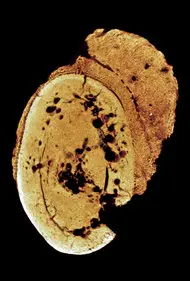

Bằng chứng sớm nhất về ung thư ở người được phát hiện từ 1,7 triệu năm trước ở loài Paranthropus Robustus hoặc Homo Ergaster, với một khối u ác tính ở xương ngón chân trái.

Bộ xương này được tìm thấy trong hang Swartkrans ở Nam Phi, nơi được gọi là “Cái nôi của loài người” vì tập trung nhiều hài cốt họ hàng của con người hiện đại.

Các nhà khoa học đã dùng phương pháp chụp cắt lớp vi tính (CT) để so sánh với các trường hợp ung thư xương hiện đại và phát hiện hình dạng đặc trưng của u xương ác tính.

Điều này được công bố trên tạp chí South African Journal of Science năm 2016.

Ngoài ra, một khối u lành tính còn cổ xưa hơn đã được tìm thấy ở loài Australopithecus sediba, sống cách đây 1,9 triệu năm.

Xương là một trong những mô ít bị phân hủy, giúp các nhà khoa học tìm ra dấu vết của ung thư trong hóa thạch.